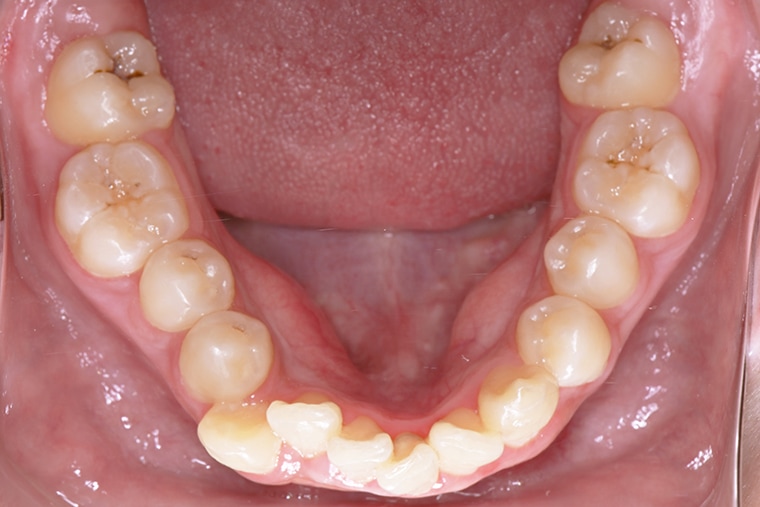

BEFORE